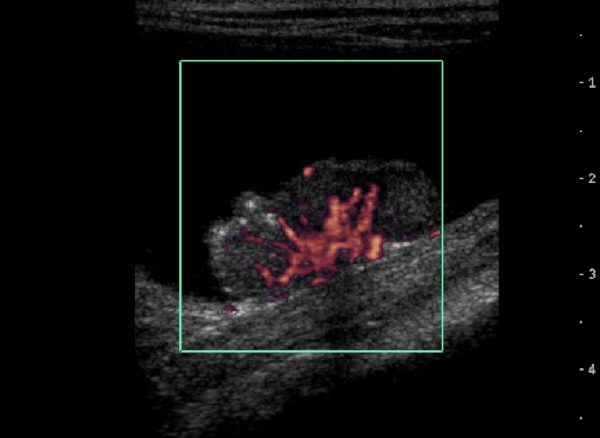

Ultrasound depicting a bladder lesion.

Bladder lesion